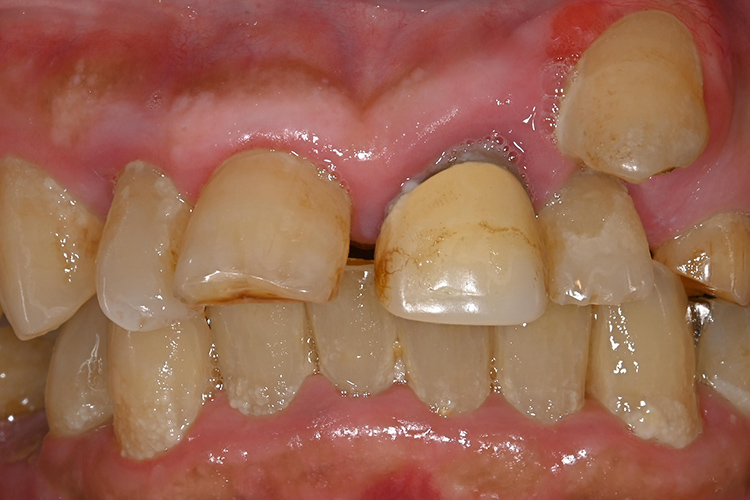

この患者様は、口腔内全体において重度の歯周病が生じており、歯磨き指導、クリーニング、Flap手術等を行ったが、歯周ポケットが深すぎるためブルーラジカル適用症例と診断し、施術を行いました。

施術前のレントゲンと口腔内写真です。施術前にプラークの除去を行ってから、施術します。